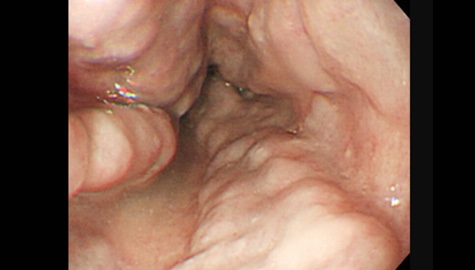

ハイビジョン内視鏡

十二指腸腺腫の内視鏡写真です。 十二指腸粘膜ひだの上に乗っかった白い扁平な隆起です。十二指腸腺腫は大きさだけでは「がん」の診断をすることは難しいと考えられています。生検でがん化の可能性が高ければ、内視鏡治療を行っていくようになります。 この段階では症状は出現しませんが、このような早期の段階で腫瘍が発見できれば、内視鏡治療が可能になるのです。